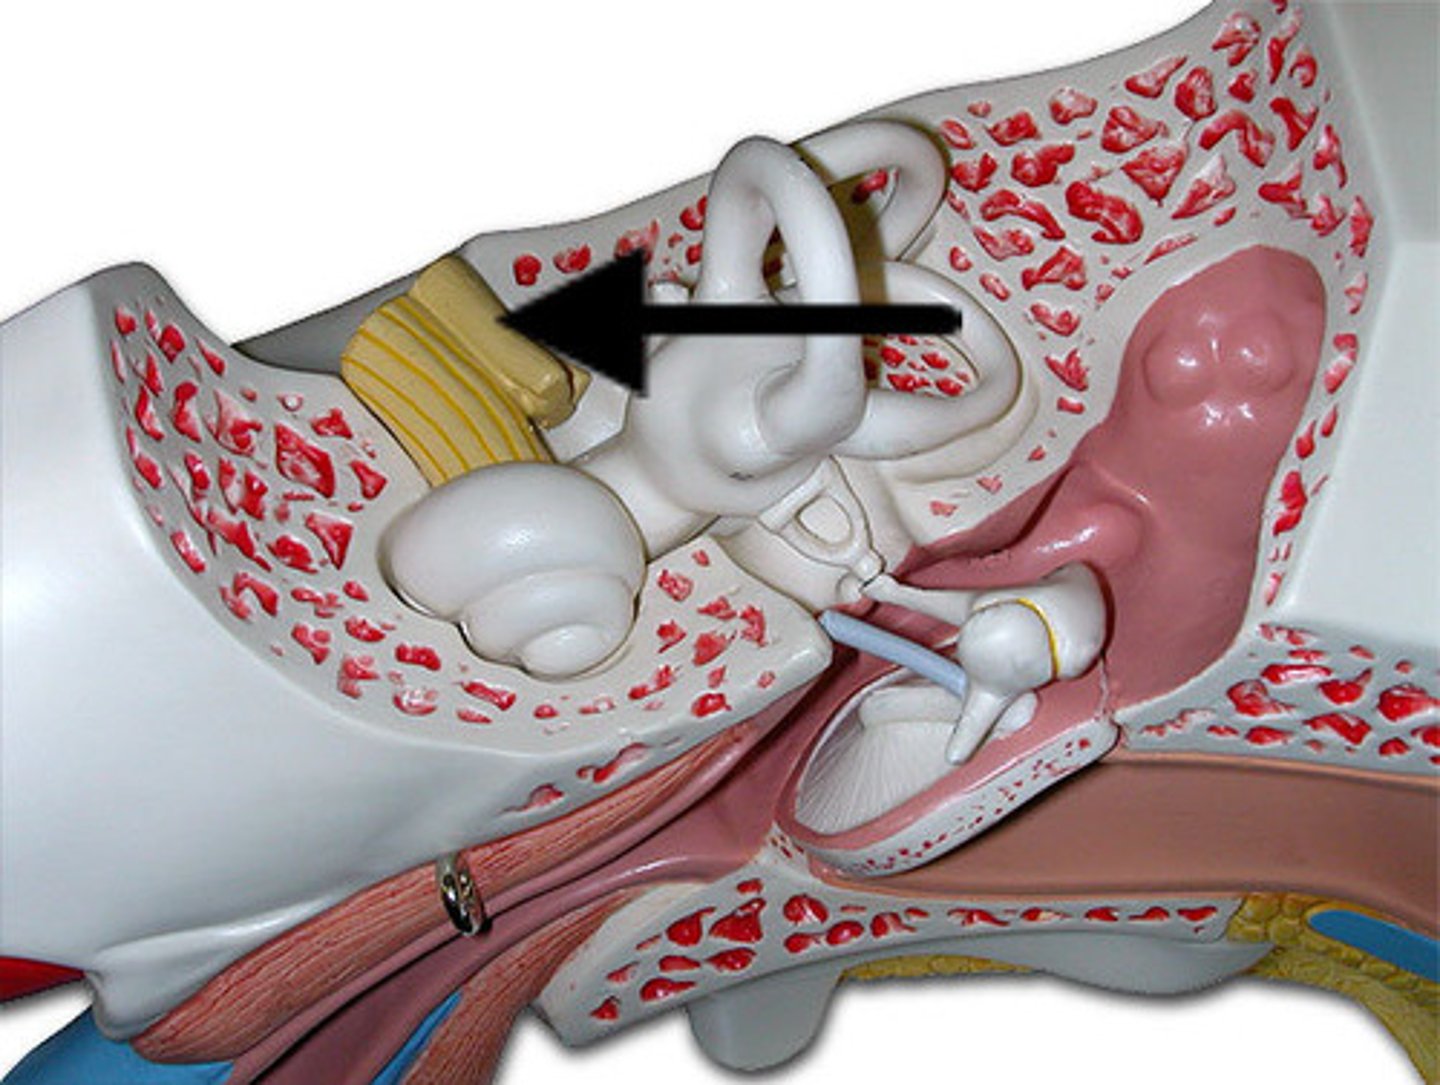

auditory tube

auricle (pinna)

cochlea

cochlear nerve

external auditory canal

incus

labyrinth (osseous + membranous)

(general structure, ignore arrow)

malleus

oval window

round window

scala tympani

section of cochlea

scala vestibuli

section of cochlea

semicircular canals

spiral organ (of corti)

section of cochlea

stapes

temporal bone

tympanic membrane

vestibular nerve

vestibule

vestibulocochlear nerve